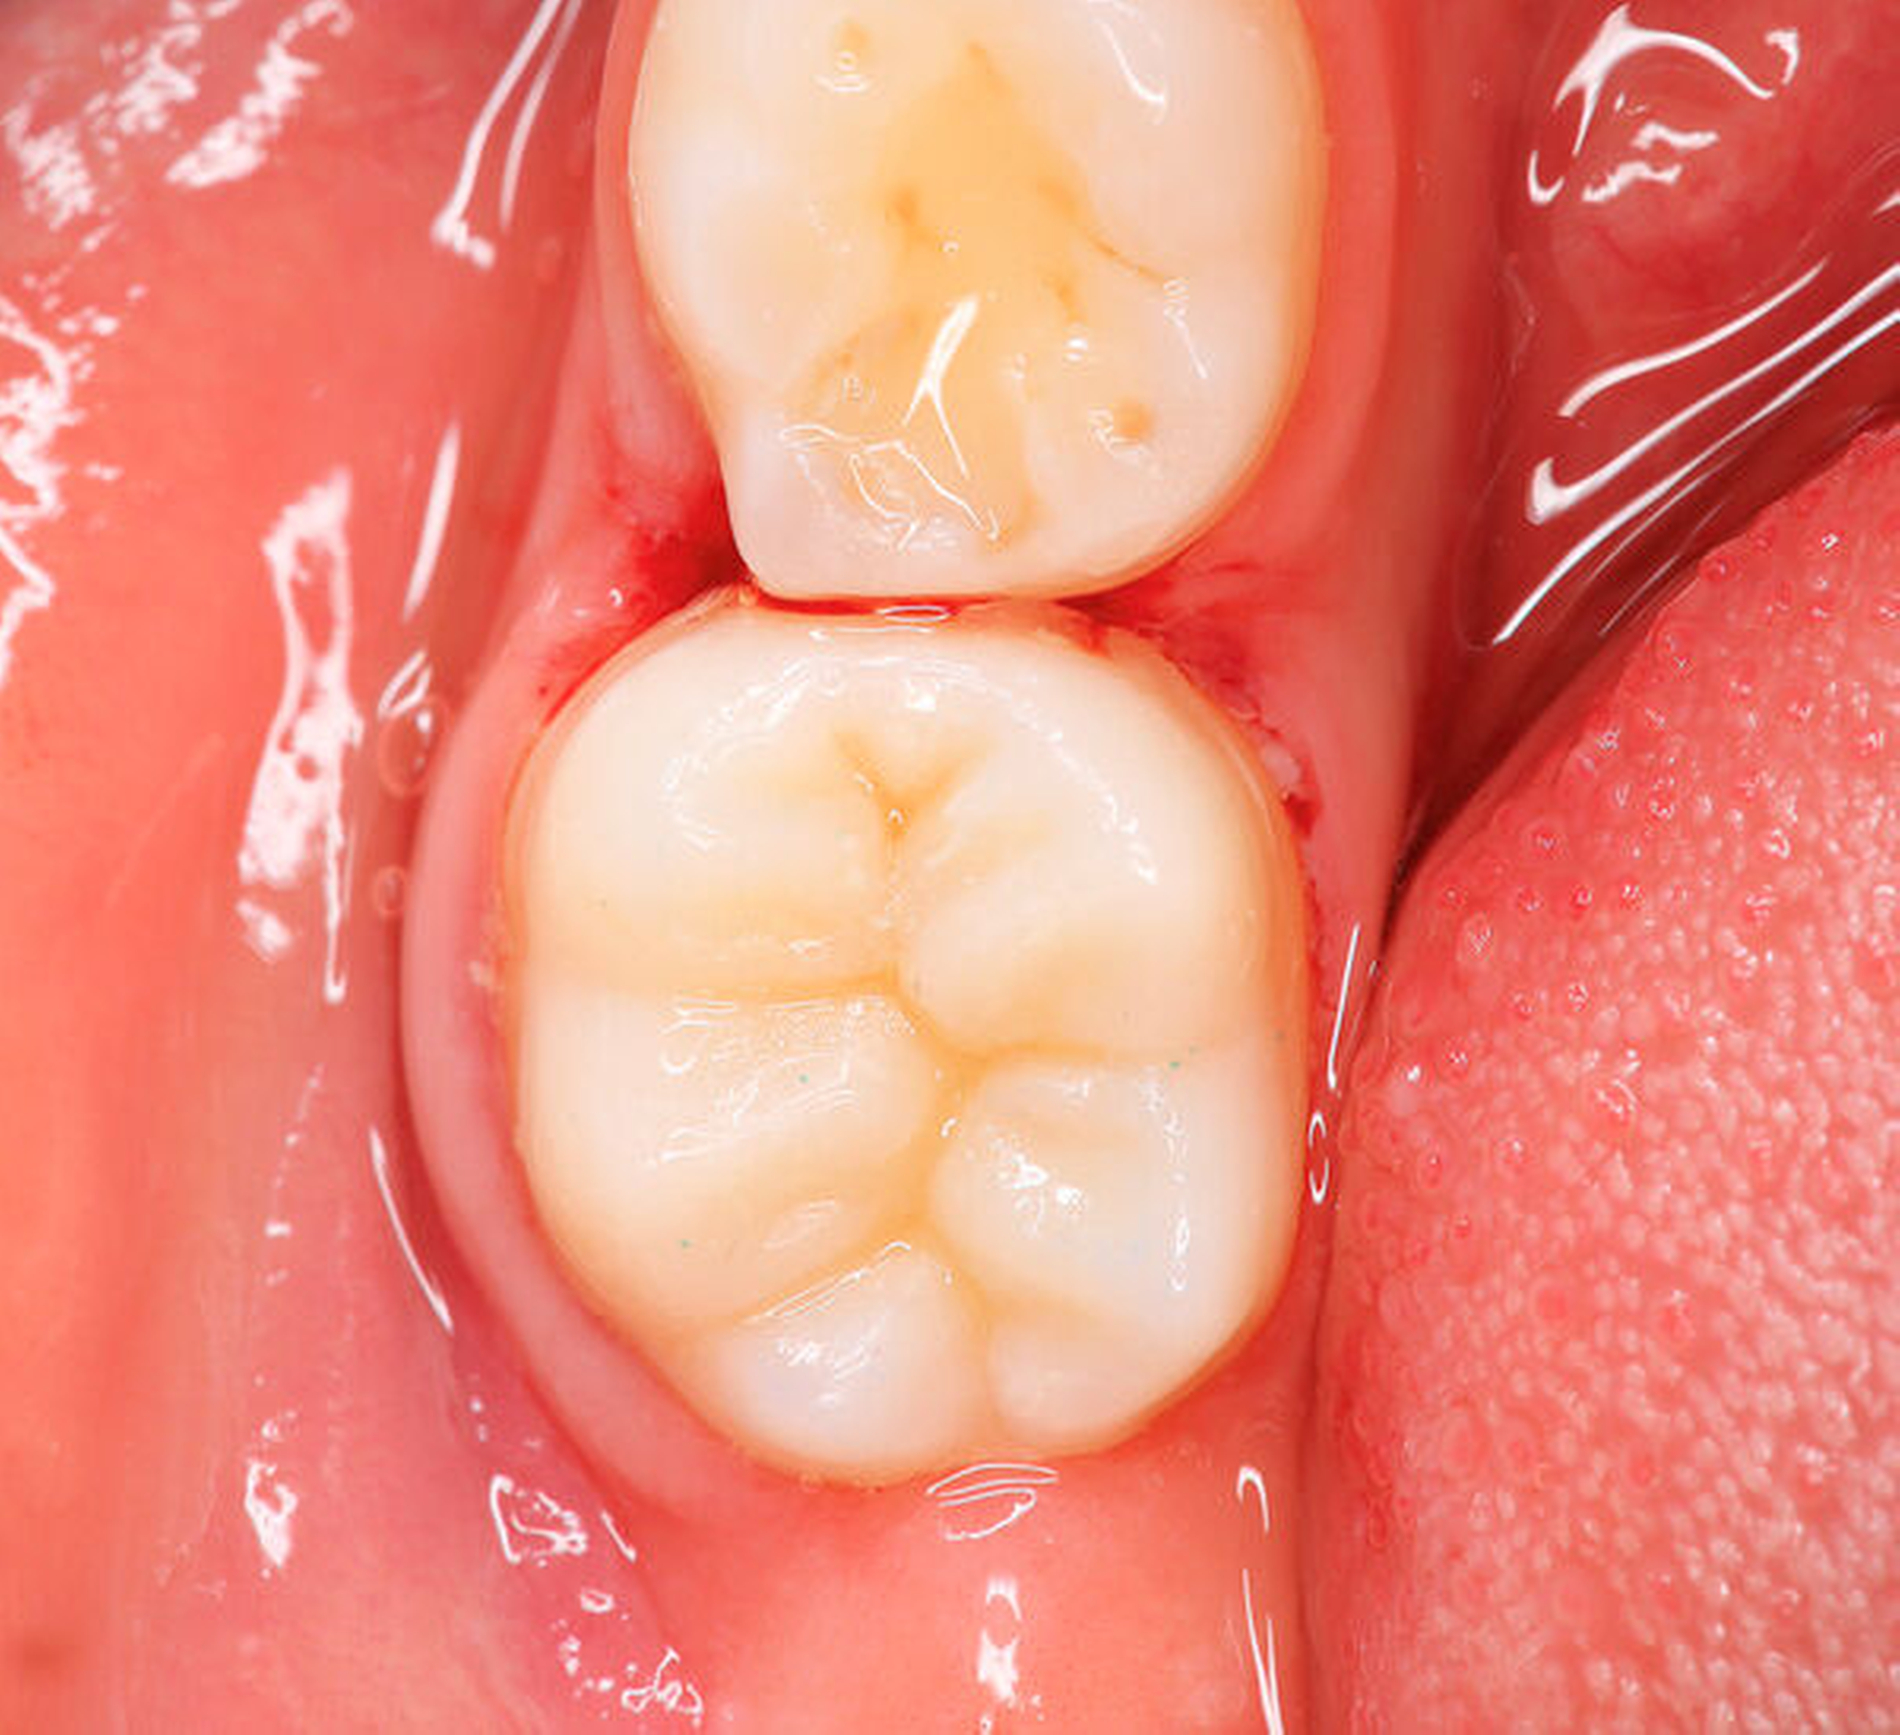

Die Ausprägung der Mindermineralisation kann stark variieren (Abbildungen 3 und 4). Klinisch zeigen sich an den betroffenen Zähnen unterschiedlich starke Verfärbungen beziehungsweise Opazitäten bis hin zu ausgeprägten Schmelzverlusten. So kann die Mineralisationsstörung im Bereich der Molaren auf einzelne Bereiche beschränkt sein, das Fissurenrelief einbeziehen oder sich über die gesamte Glattfläche erstrecken [Koch et al., 1987]. Bei den Inzisiven ist die Mindermineralisation bukkal zu finden. Geringgradig betroffene Zähne sind dabei eher durch weiß-gelbliche oder gelb-braune, unregelmäßige Verfärbungen gekennzeichnet, schwere Hypomineralisationsformen weisen dagegen abgesplitterte oder fehlende Schmelz- und/oder Dentinareale unterschiedlichen Ausmaßes auf.

Sind bei einem Patienten mehrere Molaren betroffen, so kann es auch hier zu Variationen kommen. Dementsprechend kann es sein, dass bei einem Molaren kleine, intakte Opazitäten zu finden sind, während an einem anderen Molaren große Teile des Schmelzes bereits kurz nach dessen Eruption einbrechen [Weerheijm, 2004].

Bildgruppe Abb. 7–14:Grade des MIH-Treatment-Need-Index im klinischen Erscheinungsbild